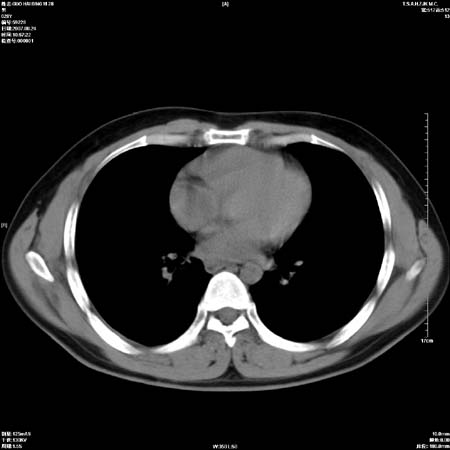

男性,28岁,体检发现左肺病变,患者只有背部隐痛感,哀哉,真不忍心下诊断啊。

左肺门区软组织肿块,左肺上叶支气管开口消失,纵隔内见肿大淋巴结,考虑左中心型肺部,可以做纤支镜取病理确认.

左肺肺门区肿块影,分叶明显,左肺上叶支气管开口受压,纵隔内见肿大淋巴结,考虑左中心型肺癌。

支持左上叶中央型肺癌伴纵隔淋巴结转移.

左上叶中央型肺癌伴纵隔淋巴结转移

左上叶中央型肺癌伴纵隔淋巴结转移.

肿块形态影像支持左上叶中央型肺癌伴纵隔淋巴结转移。

支持左上叶中央型肺癌伴纵隔淋巴结转移

支持左肺上叶中央型肺癌伴纵隔淋巴结肿大.

左侧中心型肺癌纵隔淋巴结转移。我们见一例16岁男孩,已经脑转移了。

左肺门区分叶状软组织肿块,纵隔内有肿大淋巴结,诊断肺癌应该问题不大。

肺癌并纵隔淋巴结转移。

左上叶中央型肺癌伴纵隔淋巴结转移.苦命!

左肺中心型肺癌并纵隔淋巴结转移!考虑为小细胞肺癌,没有手术机会了,只能进行放化了,疗效不错,但极易复发。没办法,现在肿瘤年轻化越来越明显了。

左上肺癌伴纵隔淋巴结转移.